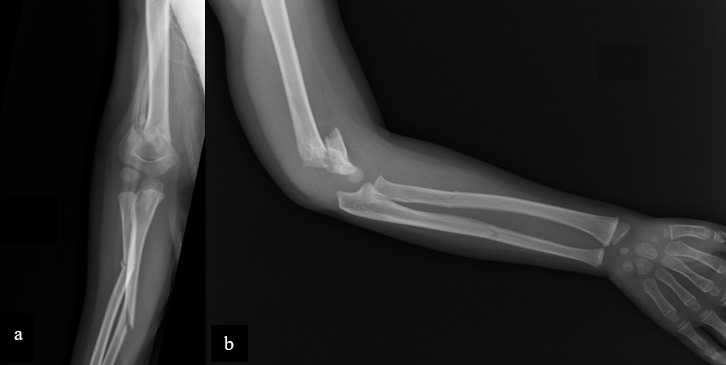

浮肘是指同侧肱骨和前臂同时骨折。这是一种不常见的损伤,极有可能导致前臂室压力升高,并可能造成破坏性的神经系统后遗症。已有多种治疗方法的报道。虽然在英文文献中已考虑过保守治疗,但在可能的情况下,经皮或微创固定是一个目标,软组织和生长板的保护对骨折愈合、活动度和骨生长至关重要。

Floating elbow is defined as concomitant fracture of ipsilateral humerus and forearm. It is an uncommon injury with high potential to develop elevated forearm compartment pressures with potentially devastating neurological sequel. Several treatments have been reported. Although conservative treatment has been considered in the English literature, percutaneous or minimally invasive fixations is a goal when it is possible, soft tissue and growth plate preservation is crucial for fracture healing, mobility and bone growth.